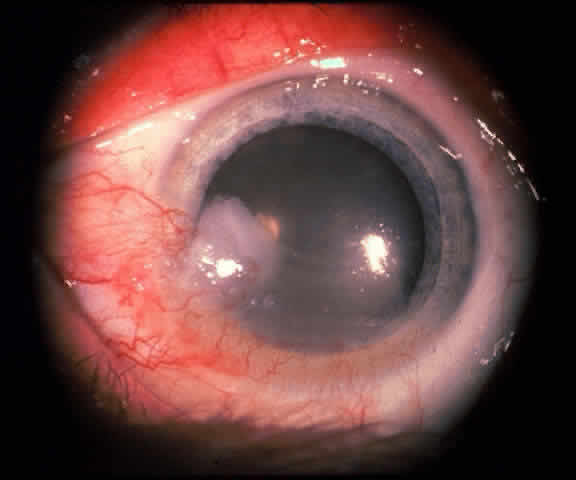

In the conjunctiva, HPV can induce papillomatous lesions (papillomas and inverted papillomas) and epithelial dysplastic lesions consisting of conjunctival intraepithelial neoplasia and squamous cell carcinoma. Conjunctival papillomas were traditionally divided into infectious, limbal, and inverted types; however, current data suggest that all types have a viral etiology. All sites of the conjunctiva can be affected, and involvement of the contiguous epithelium of the lacrimal canaliculus, lacrimal sac, and nasolacrimal duct has been noted to occur.38,61,62 Conjunctival papillomas can be pedunculated or sessile and are typically shiny, flesh-colored, and papillomatous (Fig. 1). Each papillary frond has a vascular core that is easily seen through the nonkeratinized epithelium. The papillomatosis is responsible for the typical appearance of evenly spaced vessels throughout the lesion. If keratinized, these lesions may appear whitish and dull. Papillomas can be either unilateral or bilateral, and they can be either solitary or multifocal (Fig. 2). Inverted papillomas are the least common type of papilloma in all sites, but they constitute a larger portion of lacrimal sac tumors than other periocular tumors.63,64

Fig. 1. Solitary conjunctival papilloma in fornix of immunocompetent man.

Fig. 2. Confluent conjunctival papillomata in patient with multiple recurrent lesions and chronic immunosuppression after multiple renal transplants.